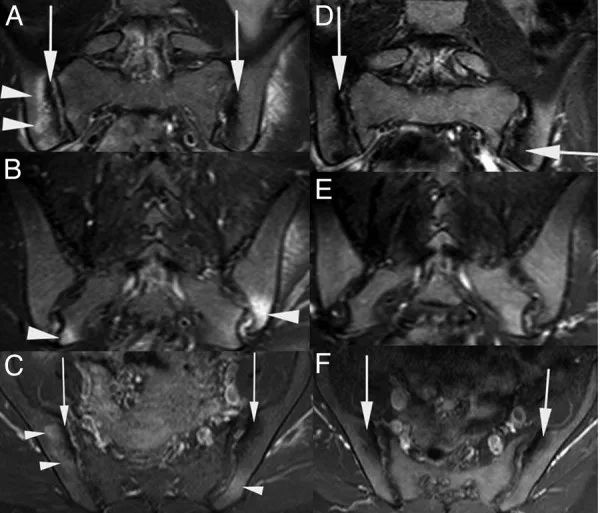

患者的风湿病相关检查显示,背痛持续5年,无慢性病史。体格检查未见外周关节炎。患者的FABERE / FADIR试验和骶髂关节受压试验阳性。实验室检查结果如下:血红蛋白10.6 g / dL,红细胞沉降率(ESR)66 mm / min 和C反应蛋白(CRP)62 mg / L。骶髂关节图显示双侧2级骶髂关节炎。骶髂关节MRI显示骶髂关节距离呈双侧相等。然而,双侧关节两侧不规则,伴有皮质侵蚀,髂翼软骨下硬化明显增加(图2)。

图2冠状位倾斜脂肪抑制T2加权(A和B)和对比增强脂肪抑制T1加权轴位(C)MRI的骶髂关节,显示双侧高信号和对比增强骶和髂区域与骨髓水肿一致(箭头)和双侧骶髂关节软骨下软骨下(箭头)。治疗后获得的冠状斜脂肪抑制T2加权(C和D)和对比增强脂肪抑制T1加权轴(E)MRI显示松散的双侧骶骨和髂骨区域与骨髓水肿和软骨下一致骶骨硬化(箭头)在双侧骶髂关节。